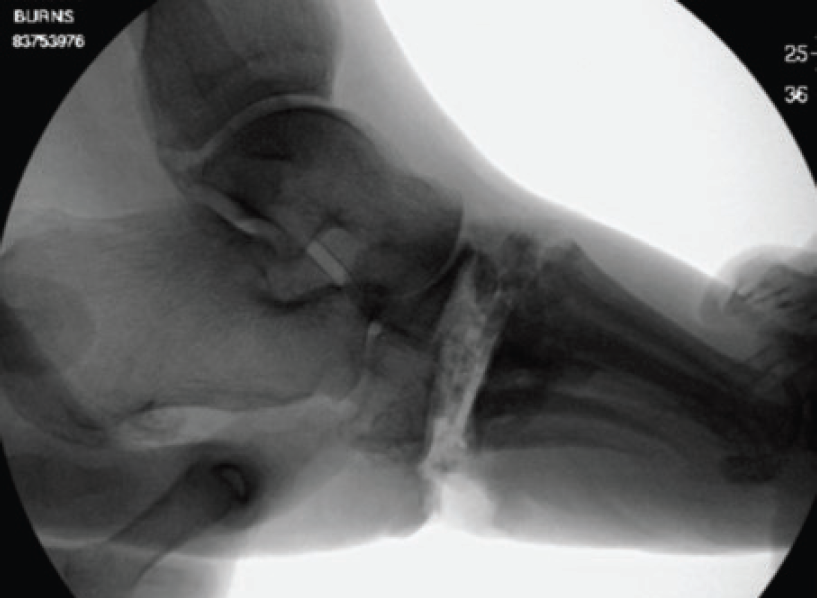

Fluoroscopy allows the surgeon to verify that the medial column is now linear (see Figure 2). One should be careful to ensure the cuboid angle is not a negative value and remove portions if necessary.